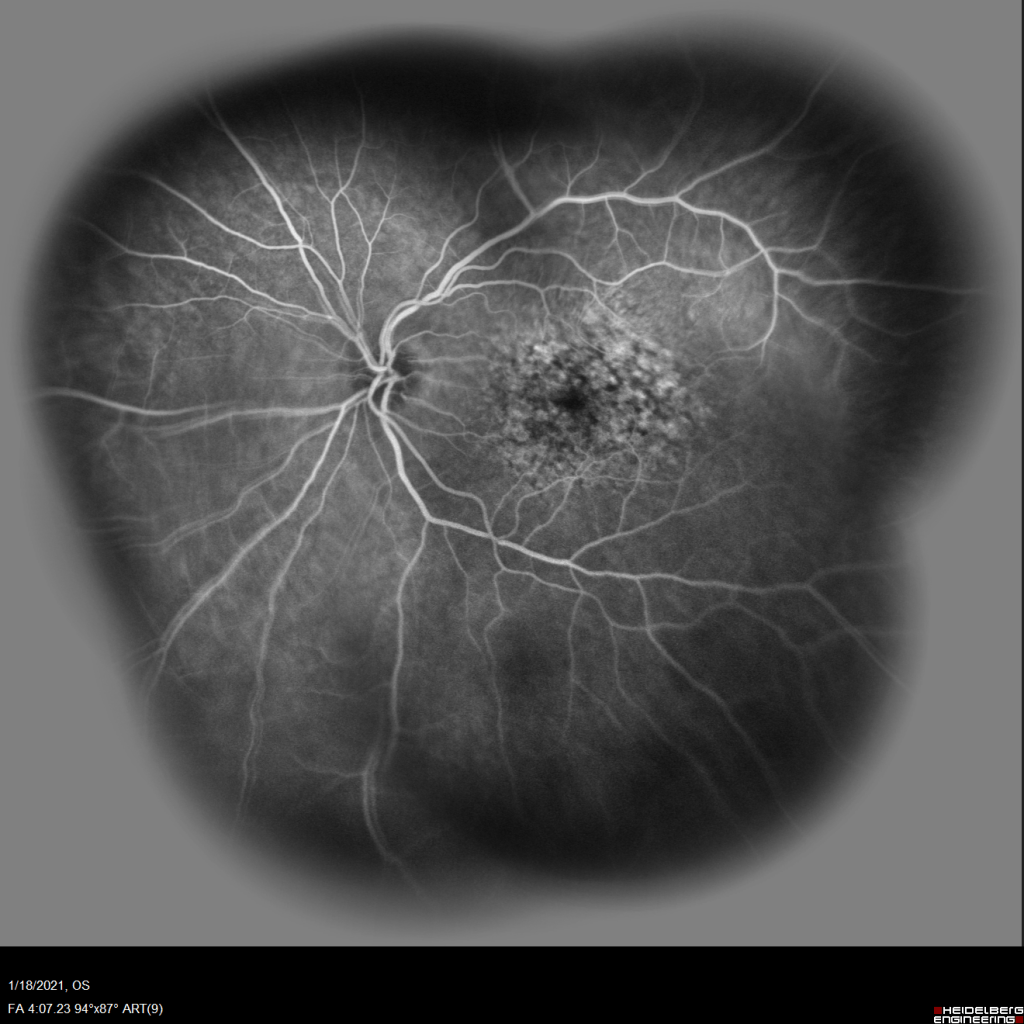

Case#1-PVH

Slowly progressive vision loss in a patient with MS.